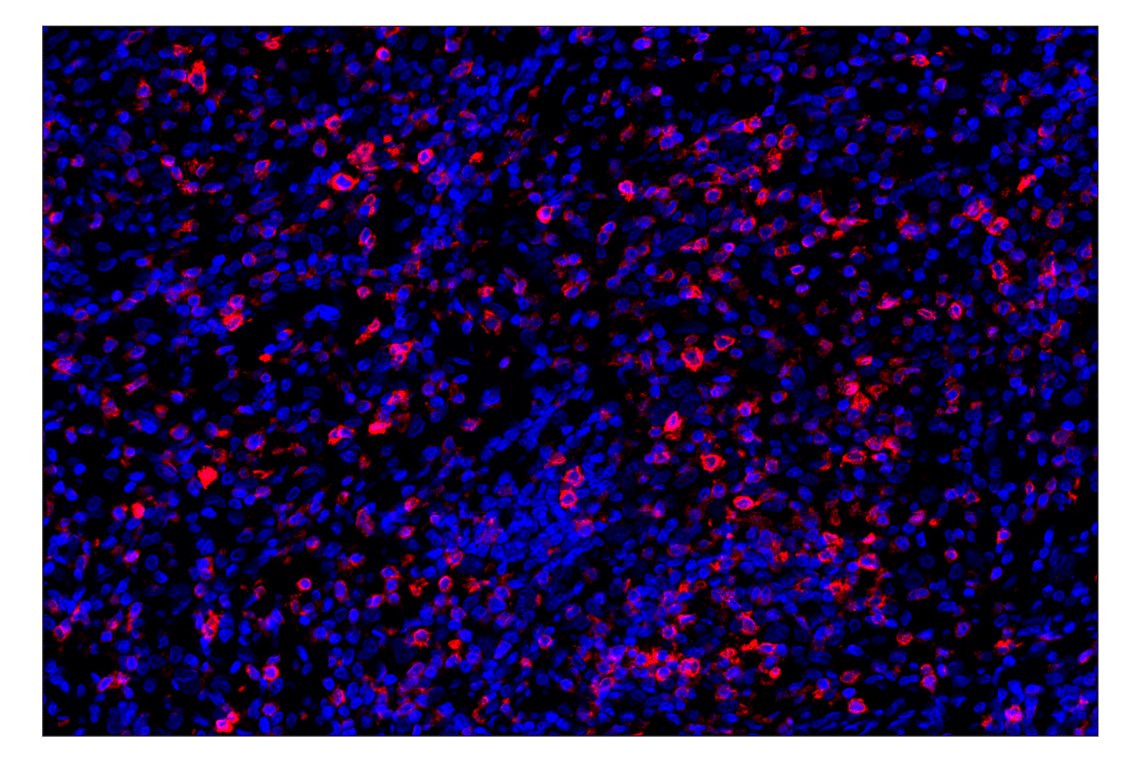

CD7 (E4G1Q) Rabbit Monoclonal Antibody (Alexa Fluor® 647 Conjugate) #41223

Immunohistochemistry (Paraffin) 1:100 - 1:400

CD7 (E4G1Q) Rabbit Monoclonal Antibody (Alexa Fluor® 647 Conjugate) recognizes endogenous levels of total CD7 protein.

Monoclonal antibody is produced by immunizing animals with a synthetic peptide corresponding to residues surrounding Leu59 of human CD7 protein.